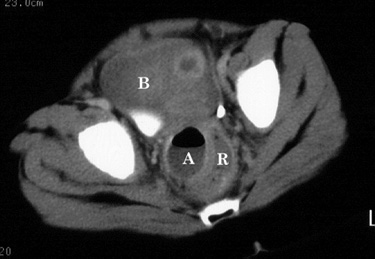

| Perforated appendicitis mimicking small bowel

obstruction. 4 year old girl presented with a four day history of anorexia, nausea, and vomiting. Physical examination was significant for pain on rectal examination. Plain films, a barium enema, and CT examination were obtained, shown below. |

|  | Figure 5. CT image at a lower level than Figure 4 shows extension of the abscess (A) deep into the pelvis, contiguous with and causing mass effect on the rectum (R). B = urinary bladder. |

| At surgery, a pelvic abscess resulting from perforated appendicitis was confirmed. |